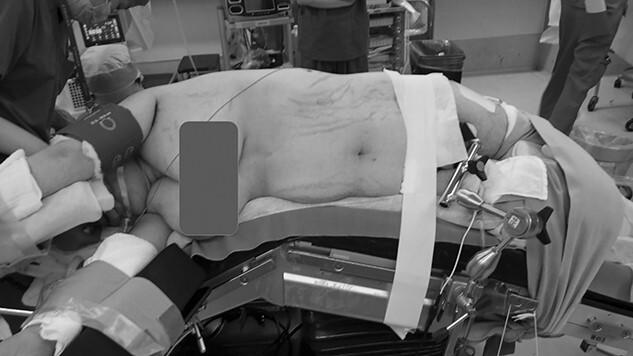

We present a case of a 42-year-old obese female with a body mass index of 38.4 kg/m. Laparoscopic tumor resection of a left nonfunctioning adrenal tumor was performed in the lateral jackknife position, and the operative time was over 5 h. After awakening, she complained right buttock pain, and we suspected bursitis due to the surgical position and decided to follow up the patient. On the second postoperative day, spontaneous pain worsened, and the computed tomography scan of the hip showed significant swelling of the gluteal muscles, which led us to suspect a gluteal compartment syndrome. Intramuscular compartment pressure was measured under general anesthesia at 72 mmHg, and a fasciotomy was performed. The symptoms improved promptly after surgery and completely disappeared 2 months after surgery. Although the gluteal compartment syndrome is a rare condition in which circulation is impaired by compression of the gluteal muscles, treatment should be initiated promptly before serious complications arise.

我们报告一例42岁肥胖女性病例,其体重指数为38.4kg/m²。在侧卧位折刀位进行了左侧无功能肾上腺肿瘤的腹腔镜肿瘤切除术,手术时间超过5小时。苏醒后,她主诉右臀部疼痛,我们怀疑是手术体位导致的滑囊炎,并决定对患者进行随访。术后第二天,自发疼痛加剧,髋部计算机断层扫描显示臀肌明显肿胀,这使我们怀疑是臀肌间室综合征。在全身麻醉下测量肌间室压力为72mmHg,并进行了筋膜切开术。术后症状迅速改善,术后2个月完全消失。尽管臀肌间室综合征是一种罕见的疾病,因臀肌受压导致循环受损,但应在严重并发症出现之前及时开始治疗。